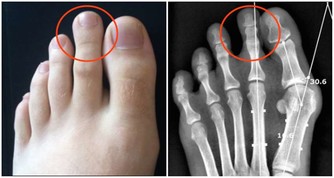

4.不凍腳

俗話說:養樹需護根,養人需護腳。腳作為人體的“第二心臟”,一旦受寒,容易引起腰腿疼痛、骨刺等問題,還會增加心血管疾病的患病概率。

建議:把涼鞋收一收,換上棉襪布鞋。家里地板是瓷磚的朋友,也別光著腳走,把鞋子穿上。

另外,平日裡可以泡泡腳,不僅能促進腳部血液循環、消除疲勞、改善睡眠,還能調整臟腑功能、增強體質。